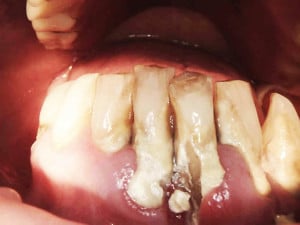

Postępowanie rozdzielono na dwie wizyty. Badaniem klinicznym, oceniając wskaźniki periodontologiczne, uzyskano wartości API 100%, PBI 100% świadczące o konieczności poprawy higieny i procesie zapalnym dziąseł, duże złogi kamienia nad i poddziąsłowego, bardzo obfity biofilm, pogłębione wszystkie kieszonki dziąsłowe, ciężkie zapalenie dziąseł, ruchomości zębów dolnych III stopnia, duży zanik kości. Badanie kliniczne błony śluzowej jamy ustnej nie wykazało zmian patologicznych.

Na pierwszej wizycie usunięto złogi kamienia nad- i poddziąsłowego za pomocą skalera ultradźwiękowego EMS oraz osady i biofilm za pomocą piaskarki airflow S2 EMS –użyto piasku AIR-Flow PLUS. Ponieważ pani jest bardzo wrażliwą osobą, a stan zapalny dziąseł był bardzo duży, pacjentka została miejscowo znieczulona do zabiegu.